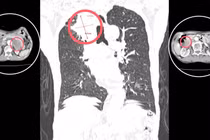

U trung thất chỉ chiếm khoảng 1-3% các khối u lồng ngực nhưng có thể gây nhiều biến chứng nguy hiểm đến tính mạng nếu không được phát hiện và xử trí kịp thời.